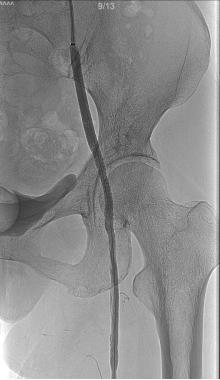

术前造影检查提示病变部位

成功开通闭塞血管